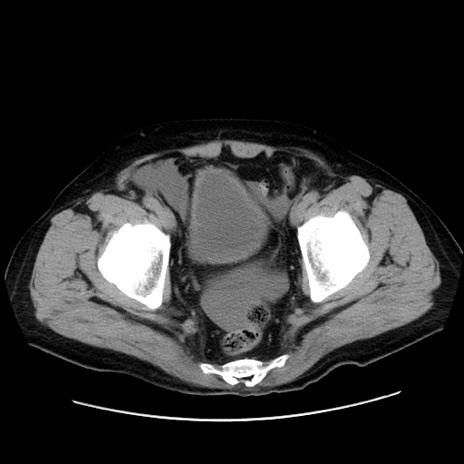

症例30(横断像)

【症例】80歳代男性

【主訴】臍周囲痛

【現病歴】約6時間前から臍下部痛が出現。次第に腹部膨隆・背部痛も生じてきたため来院。背部痛の場所は変化しない。

【既往歴】腎盂腎炎

【身体所見】意識清明、BT 36.3℃、BP  131/87mmHg、P 87bpm、SpO2 100%(RA)、臍周囲自発痛・圧痛あり、反跳痛なし、自発痛部位に一致して板状硬あり、腹部膨隆、腸雑音減弱、CVA tenderness両側陰性。

【データ】WBC 19600、CRP 0.33